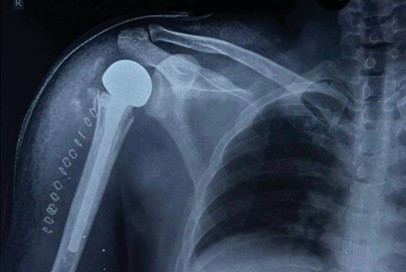

A Study on Functional Outcome of Hemiarthroplasty for Proximal Humeral Fractures – An Observational Study

Mohamed Safiullah , Venkata Kiran Pillella , Madhukar

………………………………p.388-391